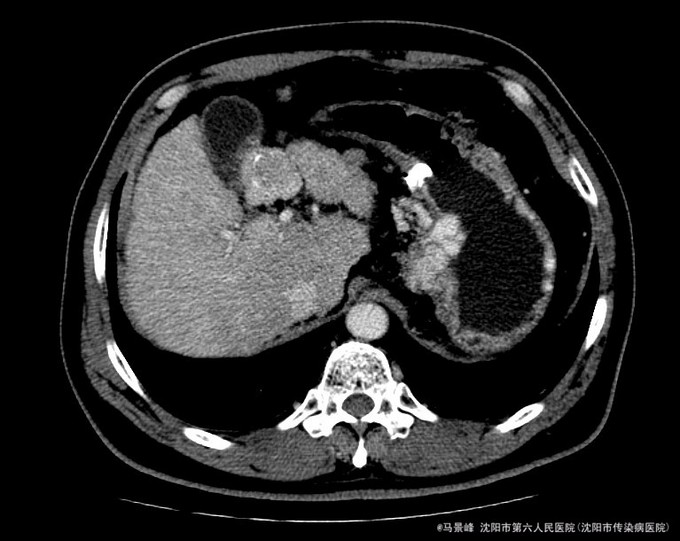

查体:巩膜无黄染,心肺听诊无异常,腹软,无压痛,肝脾肋下未触及,移动性浊音阴性,双下肢无浮肿。 入院后化验结果:丙氨酸氨基转移酶 24 U/L、天门冬氨酸氨基转移酶 36 U/L、碱性磷酸酶 101 U/L、γ-谷氨酰转肽酶 96 U/L、胆碱酯酶 6127 U/L、总蛋白 80.8 g/L、白蛋白 41.4 g/L、总胆红素 30.0 umol/L、结合胆红素 0.0 umol/L、非结合胆红素 16.5 umol/L、δ胆红素 13.5 umol/L。葡萄糖 7.77 mmol/L。乙型肝炎病毒表面抗原 阳性(+) 、乙型肝炎病毒核心抗体 阳性(+) 。甲胎蛋白 3.49 ng/mL。 CT检查示:肝脏形态不规整,肝裂增宽,肝尾叶体积相对增大,各叶大小比例失调,肝实质密度不均,肝内可见多个大小不等结节影,较大者位于肝Ⅳ段胆囊旁,其边缘可见条状碘油沉积,大小约3.3x3.05cm,增强扫描动脉期其边缘轻度强化,门脉期及延迟期扫描呈稍低密度,病灶内坏死区未见强化,其余结节无明显强化,较大者位于Ⅷ段,约1.2cm大小,延迟期呈稍低密度,门脉主干及左右支纤细,左支充盈欠佳,脾脏缺如,胆囊不大,壁增厚,其内密度均匀,胰头区可见一囊性密度影,大小约2.11cm,增强扫描无强化。肝内外胆管未见明显扩张,食管下段胃底贲门区见扩张扭曲的血管影,腹膜后未见明显肿大淋巴结。 患者CT所见胆囊旁病灶碘油流失,且动脉期仍有强化,提示肿瘤仍有血供。

诊断:1、乙肝肝硬化 失代偿期;2、原发性肝癌TACE术后 治疗:入院后除加强休息、抗病毒治疗外,行增强CT检查,发现肝癌TACE治疗后胆囊旁病灶碘油流失,且动脉期仍有强化,提示肿瘤仍有血供。遂于局麻下再次行TACE治疗。

患者术后自觉无明显不适,食欲睡眠可,尿便正常。查体:巩膜无黄染,心肺听诊无异常,腹软,无压痛,肝肋下未触及,移动性浊音阴性,双下肢无浮肿。TACE术后一周,复查CT和肝功ALP和GGT轻度升高,CT示病灶碘油沉积增加,办理出院。出院后继续抗病毒治疗,嘱其2个月后复查。